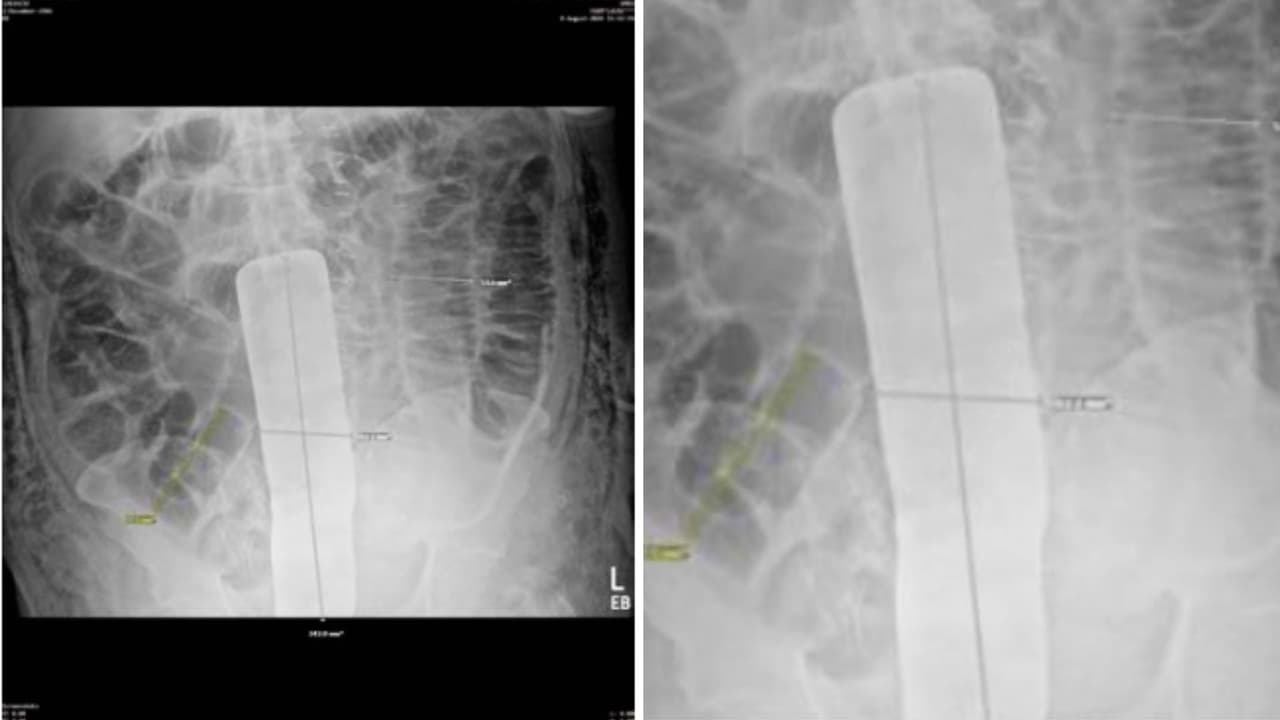

La radiografía que habló

Una radiografía abdominal reveló la verdad: un objeto metálico vertical, 24 por 6 centímetros, en la línea media de su abdomen.

Lo volvieron a abrir: Encontraron el separador y drenaron líquido intestinal acumulado.